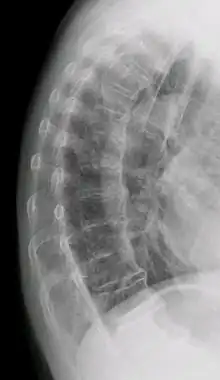

Confluent ossification of multiple contiguous vertebral bodies in diffuse idiopathic skeletal hyperostosis (DISH)